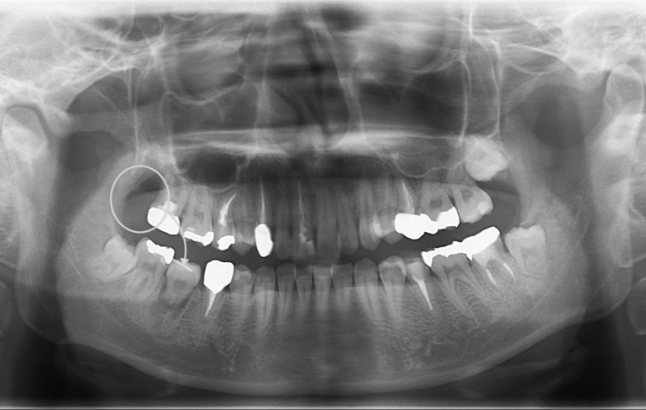

以下の写真の患者様は、移植した歯の歯根根の成長がまだ終わっていなかったため、歯を削ったり神経を取ったりすることなく、移植から11年経った現在も、そのままの状態で自分の歯として元気に機能しています。

当院では5〜10年をひとつの節目とし、炎症・咬合・審美の安定を総合的に評価。

骨量が少ない症例でも、適切な診断と手技によって高い生着率を維持しています。